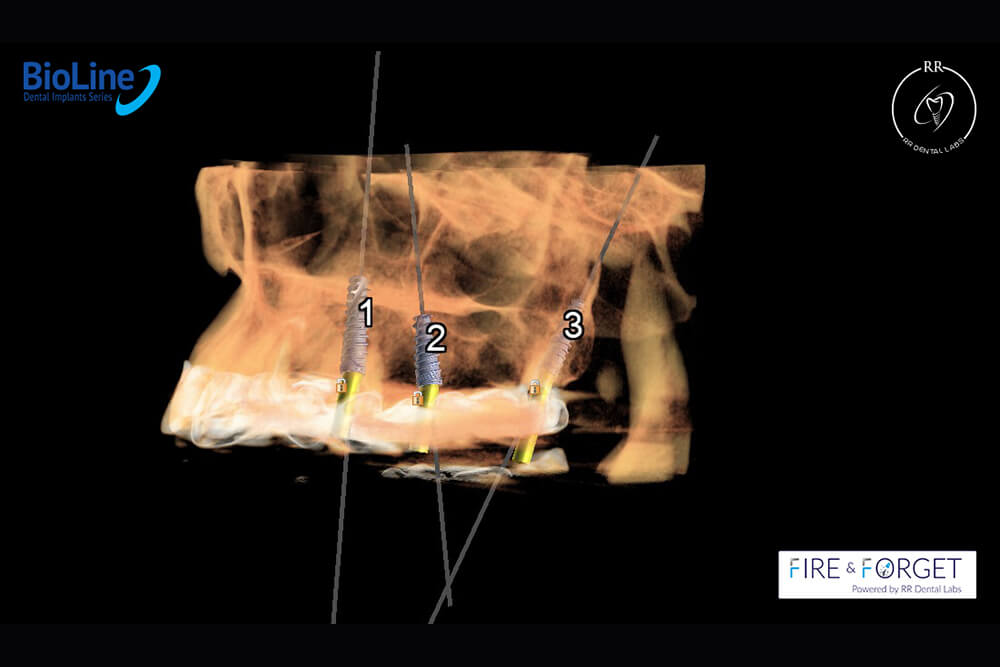

Case 47